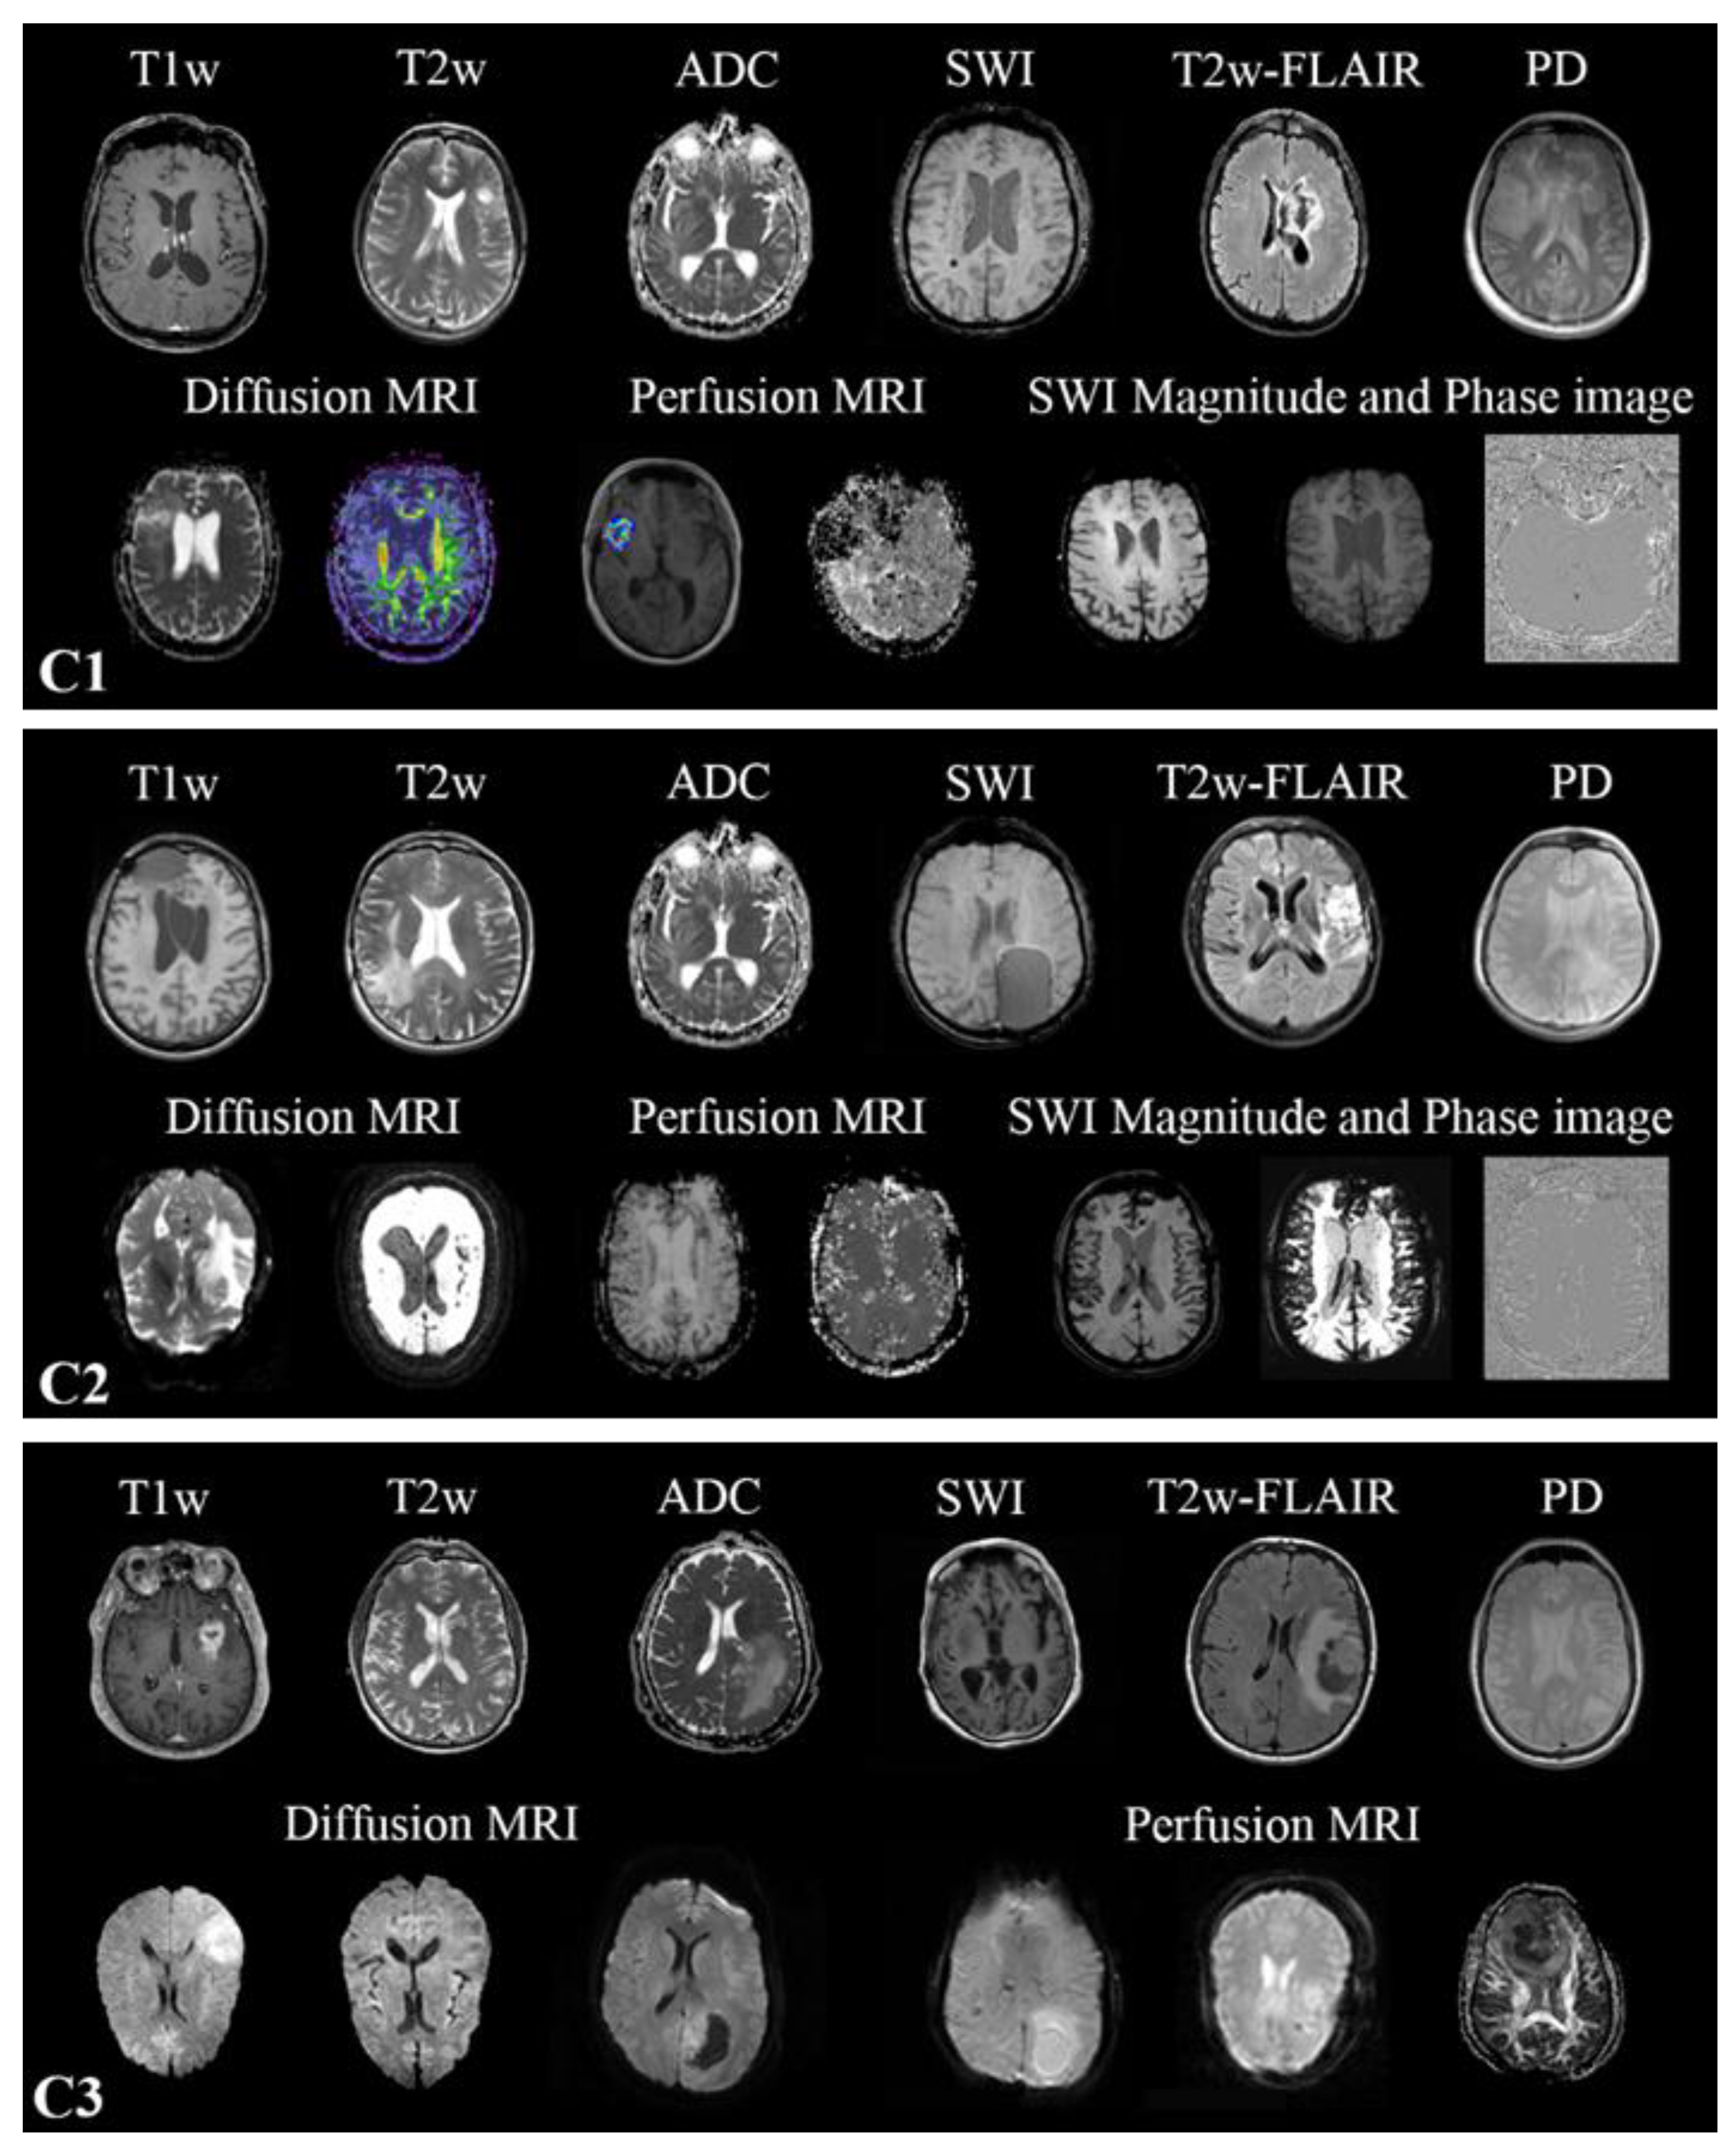

Multiparametric MRIs (mpMRI) were collected from multiple scanners in all three datasets, resulting in heterogeneous modalities and MR sequence protocols (Supplementary-Table S3). Conventional multislice (2D) acquired in the axial, sagittal, or coronal plane, as well as 3D scans, are present. The MR sequences found in the cohorts are the widely used sequences for brain tumor imaging [19] in clinical routines and trials [20,21,22]. All MR images found in the training cohort were included in the training. However, one-vs-all DCNN classifiers were only trained for T1w, contrast-enhanced T1w (T1wce), T2w, T2w fluid-attenuated inversion recovery (FLAIR), apparent diffusion coefficient (ADC), and susceptibility-weighted imaging (SWI). No SWI scans were found in C3. The in-plane resolution ranged from 0.33 x 0.33 to 2 x 2 mm for C1, 0.45 x 0.45 to 1.40 x 1.40 mm for C2 and 0.45 x 0.45 to 1.14 x 1.14 mm for C3. Slice thickness ranged from 0.9 to 7.5 mm in all MR scans. Human experts manually labeled each MR image through an in-house interactive labeling tool. The DICOM attributes "Series Description" (SD) and "Contrast/Bolus Agent" DICOM attribute were then extracted and compared to the derived labels to evaluate the metadata's consistency. Sample images found in the training and testing cohorts are shown in Figure 1.

Figure 1. Sample images of the different MR images present in the three datasets C1-C3.